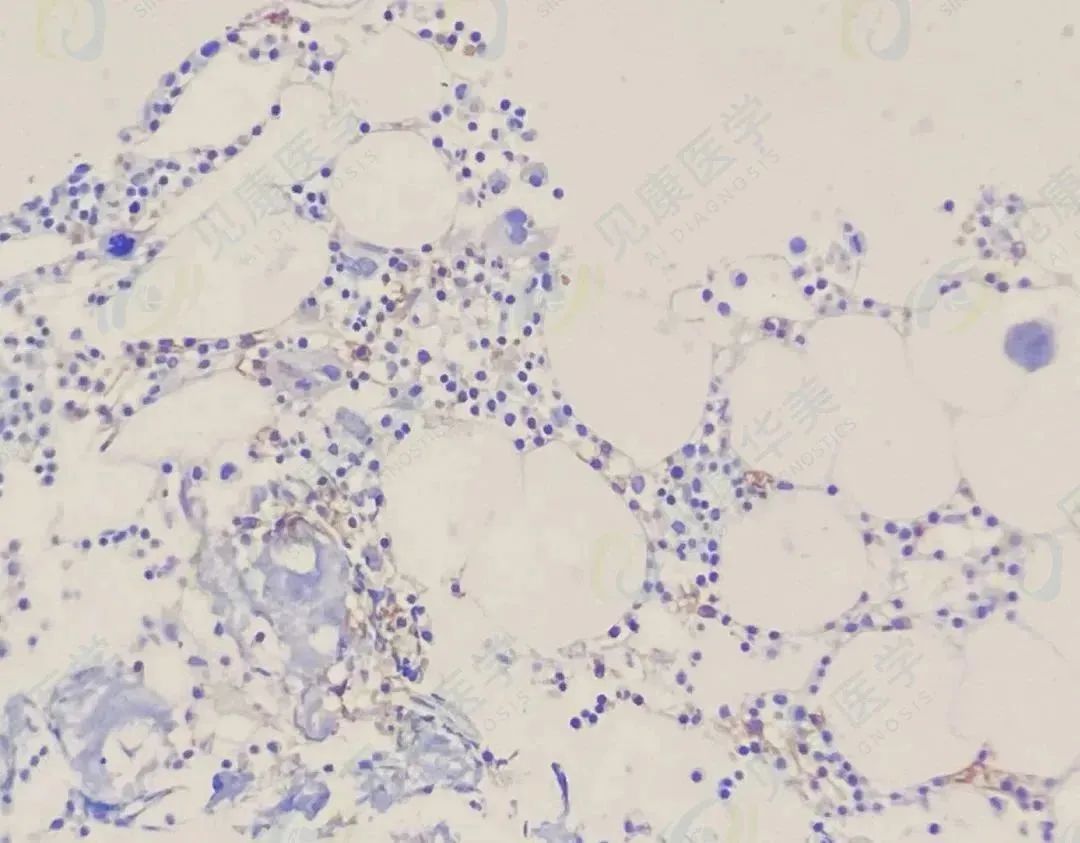

【形态学病例分享】第七十二期

患者基本信息:

男,60岁, 贫血待查。

骨髓涂片

肿瘤细胞骨髓约52%,外周血约11%。

病理

诊断结果

浆细胞肿瘤,考虑浆细胞骨髓瘤。